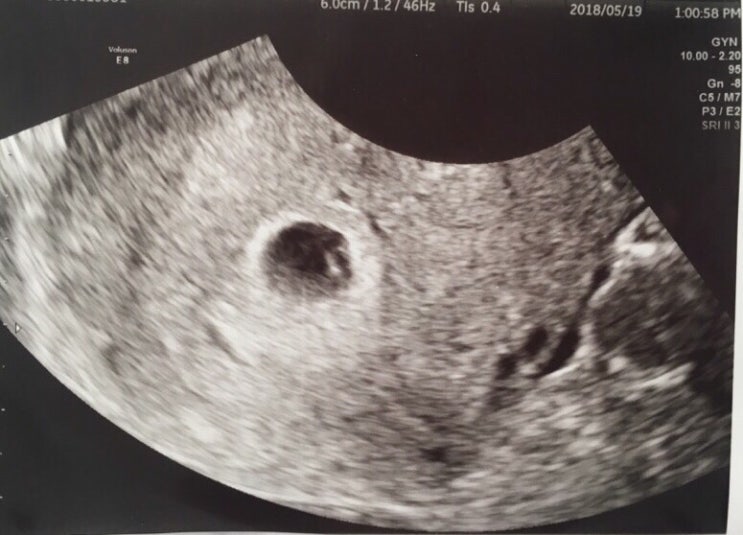

태명은 뽐이에요:) 난황이 생김! (임신 5주차 증상)

태명은 뽐이에요:) 난황이 생김! (임신 5주차 증상)280days 앱 드디어 나도 깔았다 :) 올챙이 같이 넘 귀여...